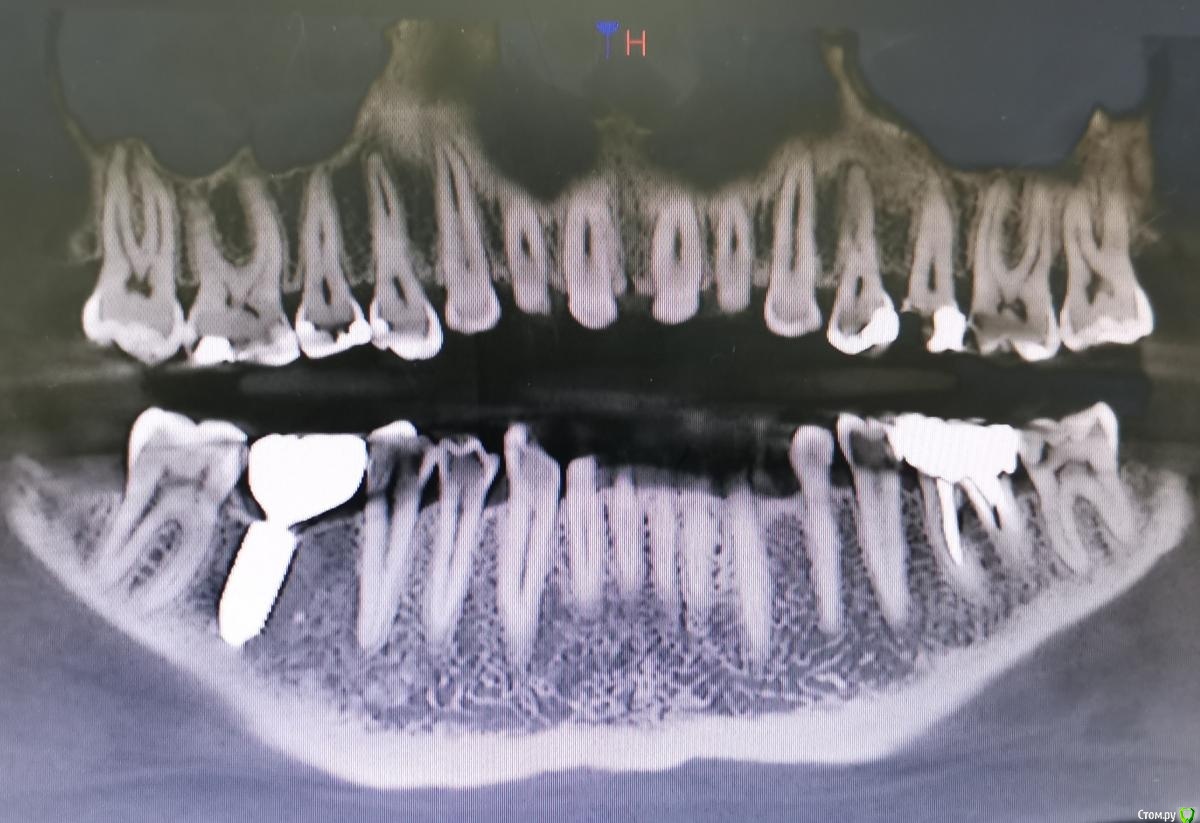

Сделала к-т для следующего врача и сделала фото с к-т. Можете посмотреть, тяжёлый ли пародонтит во всей челюсти и особенно около левых верхних зубов с 4 по 7. Как лечиться и куда бежать?

Добрый день. Тяжелой степени парадонтита по снимку точно нет.  Все остальное нужно смотреть очно.